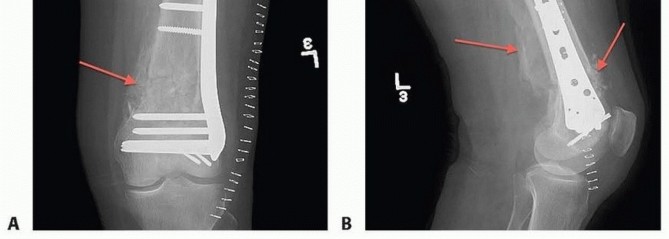

### FIG 14 • A,B. Two-week postoperative radiographs of patient from FIG 9 who underwent delayed ORIF at 5 weeks post injury. These radiographs exhibit the abundant amount of callus present (red arrows) after successful ORIF with reestablishment of length, alignment, and rotation was accomplished with takedown of the callus. The injured hip is imaged and internally rotated by the hip bump so that duplication of the profile of the normal side is achieved. The size of the bump may be adjusted as needed for the amount of rotation required. The injured knee is placed in the patella-up position to confirm rotation. This technique is helpful in comminuted metaphyseal fractures where the rotation is difficult to assess or in cases where the metaphyseal component will not be directly visualized. Even though the distal segment is not in “fixed” rotation, this technique is useful to minimize the chance of a malrotation during definitive fixation. A sterile tourniquet is used unless a temporary fixator prevents its placement. A large bump or a sterile triangle is used under the knee. This allows for knee flexion, relaxing the gastrocsoleus complex and facilitating the reduction. A sterile and removable one is most useful. The C-arm is brought in from the opposite side. It should be angled so that it is parallel with the femoral shaft. 477

### FIG 17 • A. Patient in FIG 3A after débridement of nonviable extruded bone and placement of external fixator. The segmental bone loss is seen. B,C. Nonunion of a C3 distal femur fracture with subsequent hardware (plate) failure. D,E. Early hardware failure at 3 months (screws) in a C1 distal femur fracture. It has been suggested that the use of a longer plate (longer than nine holes in length with eight holes proximal to the fracture) can minimize failures of fixation. 14 Neurovascular injuries Can occur from initial trauma Rare after surgery Infection 0% to 10% rate after ORIF Predisposing factors High-energy injuries Open fractures Extensive dissection Prolonged operative time Inadequate fixation Nonunion 0% to 19% rate after ORIF Predisposing factors Bone loss or defect ( FIG 17A) High-energy injuries Soft tissue stripping Loss of osseous vascularity Inadequate stabilization No bone graft Infection Malunion More common with nonsurgical treatment, which results in varus and recurvatum Operative treatment with newer locking plates can result in valgus. Malrotation has been reported as high as 38.5%. 2 Treatment required to restore mechanical axis Supracondylar osteotomy Stable fixation Early range of motion Hardware failure occurs in 0% to 13% of cases ( FIG 17B,C, plate; D,E, screws).14, 17 Predisposing factors Comminution of metaphyseal area Older age Very distal fracture Premature loading or weight bearing Open fractures Smoking Increased BMI Shorter plates (less than nine holes of overall length) Diabetes Nonunion Infection Knee stiffness: Almost all patients exhibit some loss of motion. Protruding hardware (see FIG 10E,F) Articular malreduction 491 Adhesions Intra-articular Ligamentous-capsular contractures Muscle scarring Treatment may consist of any or combination of the following: Manipulation Arthroscopic lysis Formal quadricepsplasty Posttraumatic arthritis occurs in 0% to 30% of cases. Predisposing factors Severe articular comminution Cartilage loss Cartilage impaction or damage Surgical factors Failure of anatomic reduction Malalignment of fracture ##